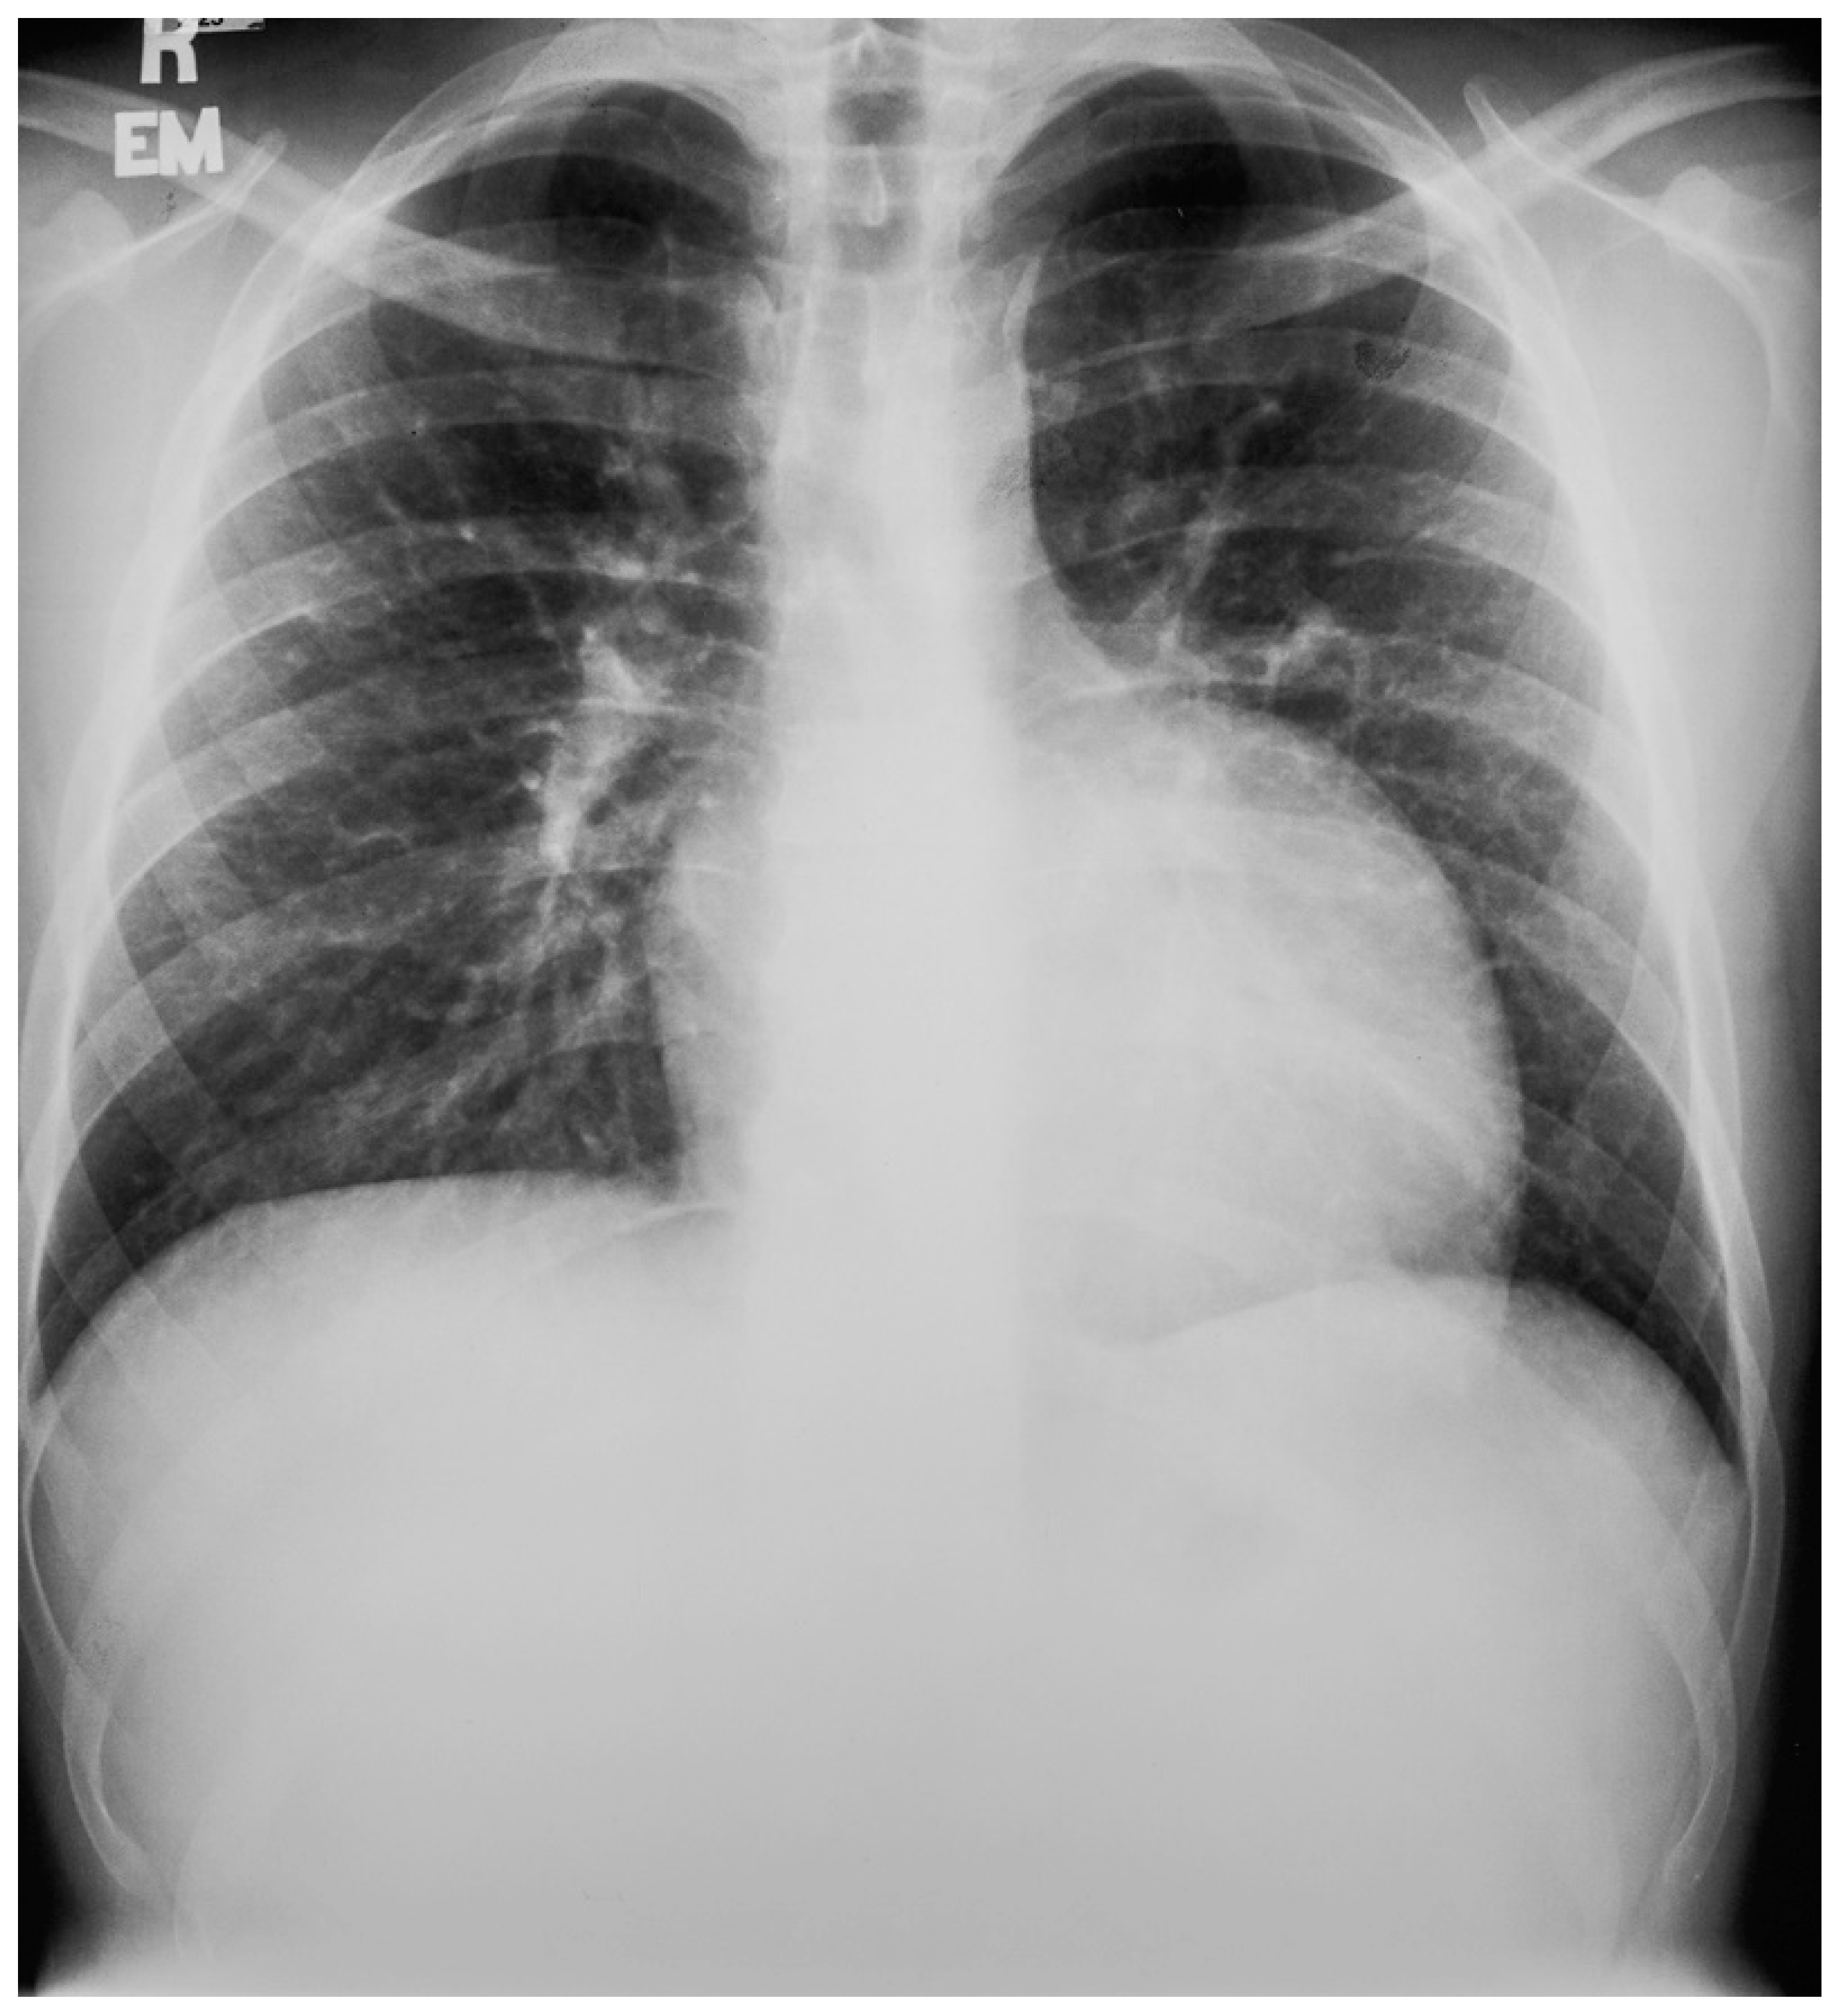

Figure 13.

Posteroanterior chest X-ray in congenitally corrected transposition of the great arteries in adulthood: This is a PA chest X-ray of a 41-year-old male who was diagnosed with congenitally corrected transposition of the great arteries (CCTGA) shortly after birth. He underwent surgical closure of a large atrial septal defect (ASD) while still under the care of a pediatric cardiologist. He remained asymptomatic and regular care was not continued as an adult. When he developed rapid atrial fibrillation with reduced functional capacity he sought medical attention and completed a chest X-ray. The image is well centered and the inspiration is good. There is mesocardia where the cardiac apex is pointing midline. The cardiothoracic ratio is <0.5. The bifurcation of the trachea demonstrates an obtuse angle between the main bronchi. This suggests left atrial enlargement, which likely accounts for the onset of atrial fibrillation. The left hilum is larger than expected for CCTGA, but this might be related to the previously-repaired ASD. The pulmonary vascularity is normal.